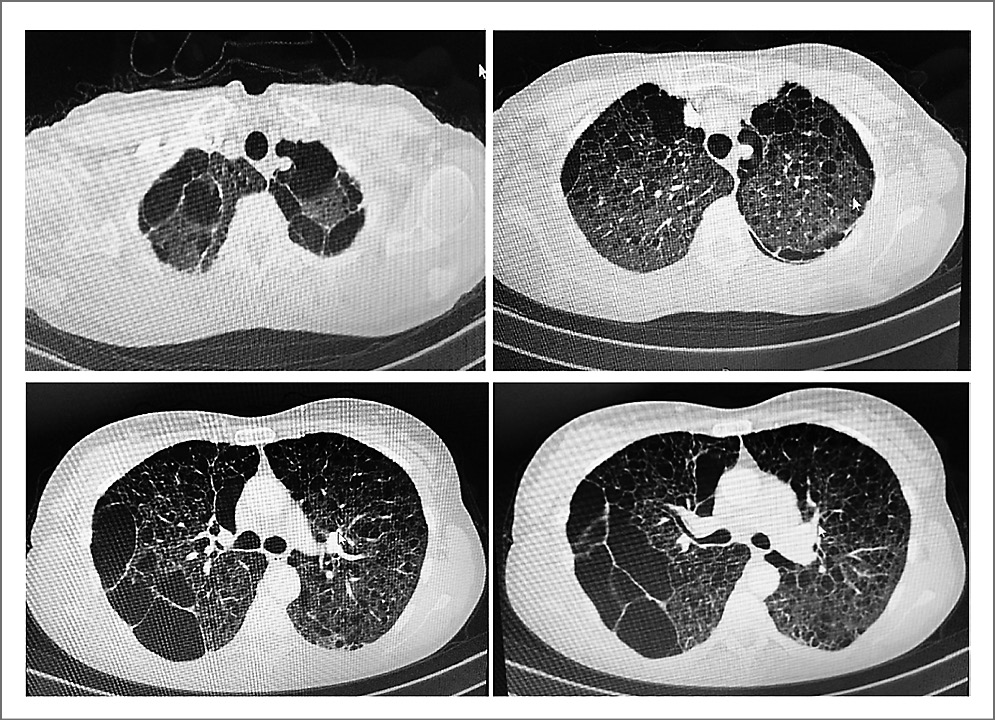

КТВР – оптимальный метод лучевой диагностики ЛАМ. Типичными КТ-признаками считают наличие четко очерченных округлых тонкостенных кист разных размеров от едва различимых до 25–30 мм в диаметре, расположенных симметрично в обоих легких и равномерно по всем полям; количество – от единичных кист до почти полного замещения ими легочной паренхимы [5].

При КТВР органов грудной клетки (апрель 2019 г.) наблюдали множественные тонкостенные кисты до 10 мм во всех отделах; в верхней и средней долях правого легкого – множественные субплевральные буллы (рис. 1).

Рис. 1. Компьютерные томограммы органов грудной клетки пациентки Б от 04.04.2019.